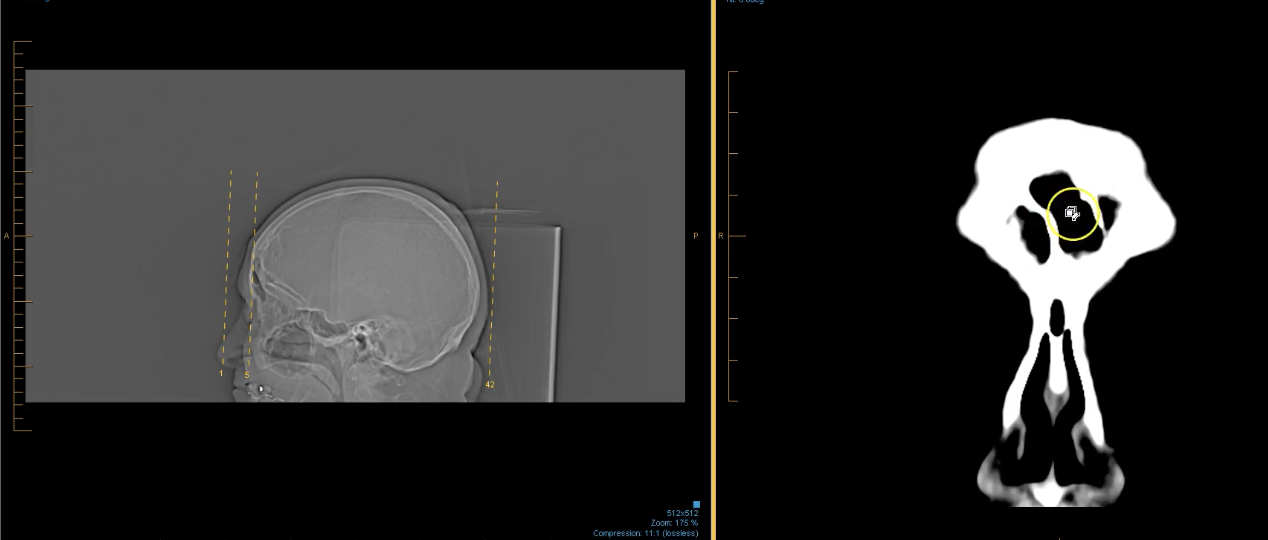

term image

right retroorbital mass. 8mmx9mm puts force on R orbital nerve